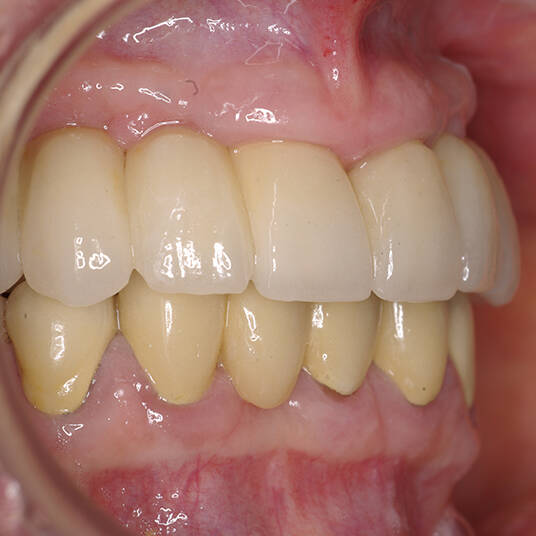

Na Clínica Pontes Odontologia, somos referência em implantes dentários em Fortaleza, oferecendo tratamentos de alta qualidade e tecnologia de ponta. Os implantes dentários são estruturas de titânio posicionadas cirurgicamente no osso maxilar ou mandibular para substituir as raízes dos dentes ausentes. Essa técnica permite a fixação de próteses personalizadas, restaurando a função mastigatória, a estética e a autoestima dos nossos pacientes.

Utilizamos a tecnologia CAD CAM, um sistema avançado que possibilita a confecção precisa das próteses dentárias diretamente sobre os implantes. Esse método inovador garante um ajuste perfeito, um resultado estético superior e proporciona muito mais conforto e durabilidade. Com o CAD CAM, nossos pacientes contam com um processo mais rápido e previsível para alcançar o sorriso desejado.